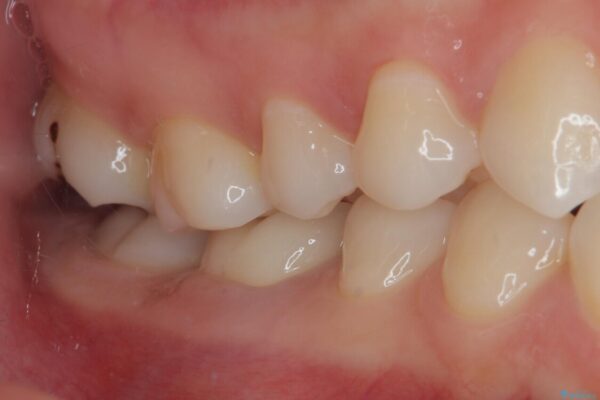

治療後

• ラバーダム使用で再感染リスクを抑えた再根管治療+精密な補綴による長期安定を実現 治療後画像

当院ではラバーダム防湿をし、根管内の感染源をしっかりと除去するために再根管治療を行いました。

その後、ファイバーコア(グラスファイバー製の支台)を築造し、最終的には精密な適合性と審美性に優れたオールセラミッククラウンによる補綴をしました。

このセラミッククラウンは、歯科技工士と連携し、1本1本の形・色・噛み合わせまで細部にこだわって製作しており、見た目の自然さだけでなく、長期的に安心して噛める機能性も重視しています。